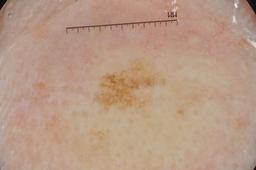

{

"age_approx": 75,

"anatom_site_general": "upper extremity",

"concomitant_biopsy": true,

"diagnosis_1": "Benign",

"diagnosis_2": "Benign epidermal proliferations",

"diagnosis_3": "Solar lentigo",

"diagnosis_confirm_type": "histopathology",

"image_type": "dermoscopic",

"lesion_id": "IL_0536025",

"melanocytic": false,

"sex": "female"

}